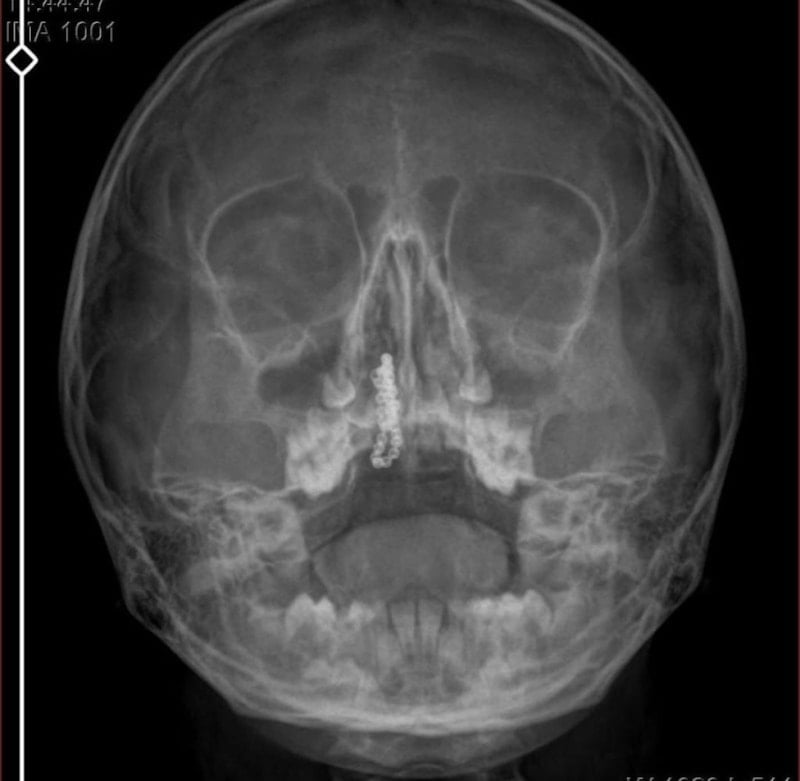

Devlet hastanesindeki doktorun incelemesi ve kapsamlı röntgen çekilmesi sonrası Polen'in burnunda, metal cisim olduğu fark edildi.

2 yıldır burunda kaldığı değerlendirilip, küçük top şeklinde tırnak makası zinciri olduğu belirlenen cisim, başarılı ameliyatla çıkarıldı.

Zincir, 2 yıldır burnunda ve devletimizin hastanesinde iyi bir doktorumuz zinciri ortaya çıkarıyor, kızım ölümden dönüyor. Ben sonuna kadar bu işin peşini bırakmayacağım. Sonuna kadar hukuk mücadelesi vereceğim. Bu da diğer hastalarımıza ibret olsun. İşte, bakın koca bir zincir. 'Bulguya rastlanılmadı' deniliyor." dedi.

Kızının ameliyat sonrası durumunun iyi olduğunu söyleyen Tekin, "İnanır mısınız bize 'Evde soba mı yanıyor? Acaba kömür isten dolayı mıdır bu?' dendi. Böyle bir şey olabilir mi? Ameliyattan çıkan parmağım kadar zincir. Devlet hastanesindeki doktor da 'Bu nasıl gözden kaçılabilir? Böyle bir pozisyon nasıl görülmeyebilir?' yorumunda bulundu. Allah'a şükür olsun atlattık.